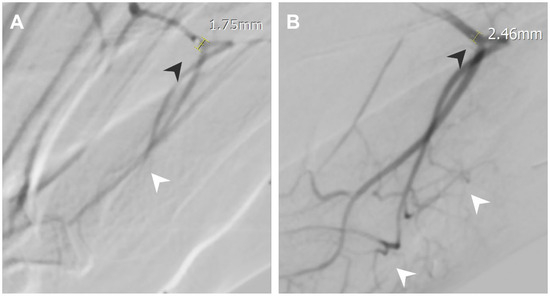

3.2. Post Traumatic Foot Pain

| Post-traumatic foot pain | Arcuate artery | 1.75 | 2.46 |